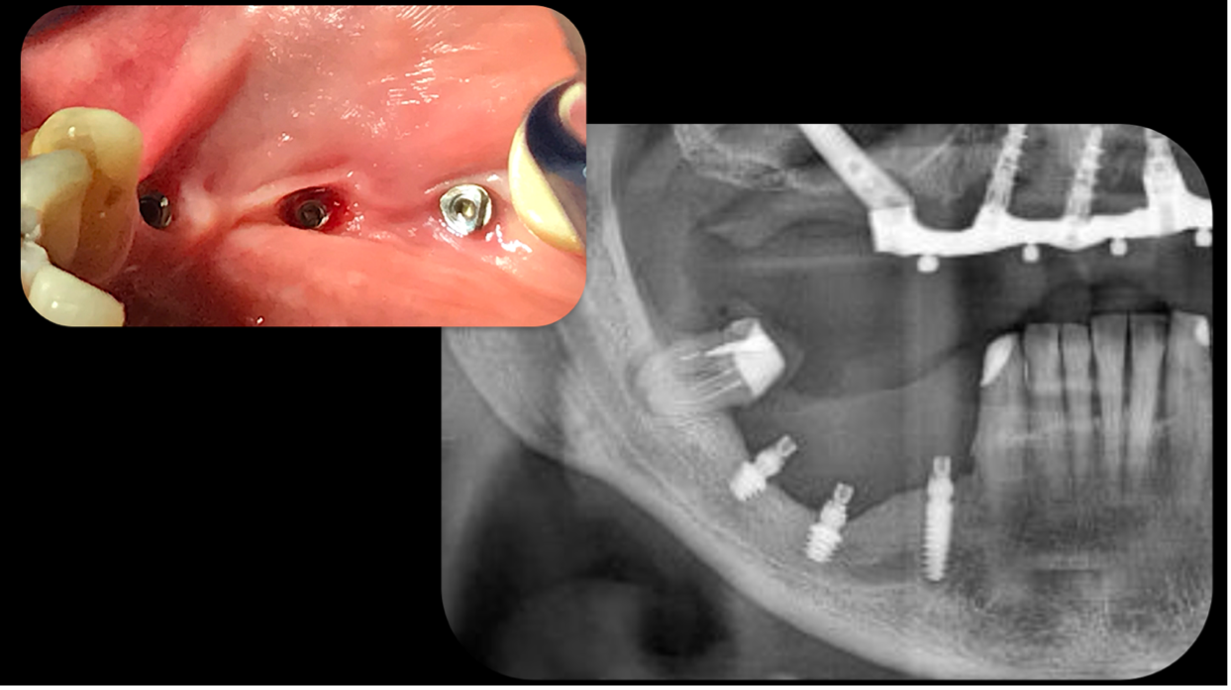

Nel secondo caso, invece, viene affrontata una situazione clinica complessa (Figura 4).

Il paziente, maschio, 63 anni, di etnia caucasica, è stato riabilitato dapprima con impianti tradizionali e impianti zigomatici; successivamente, viene programmato un intervento di implantologia guidata (Figura 5) per gestire la grave atrofia del settore 4 (Figure 6-7).